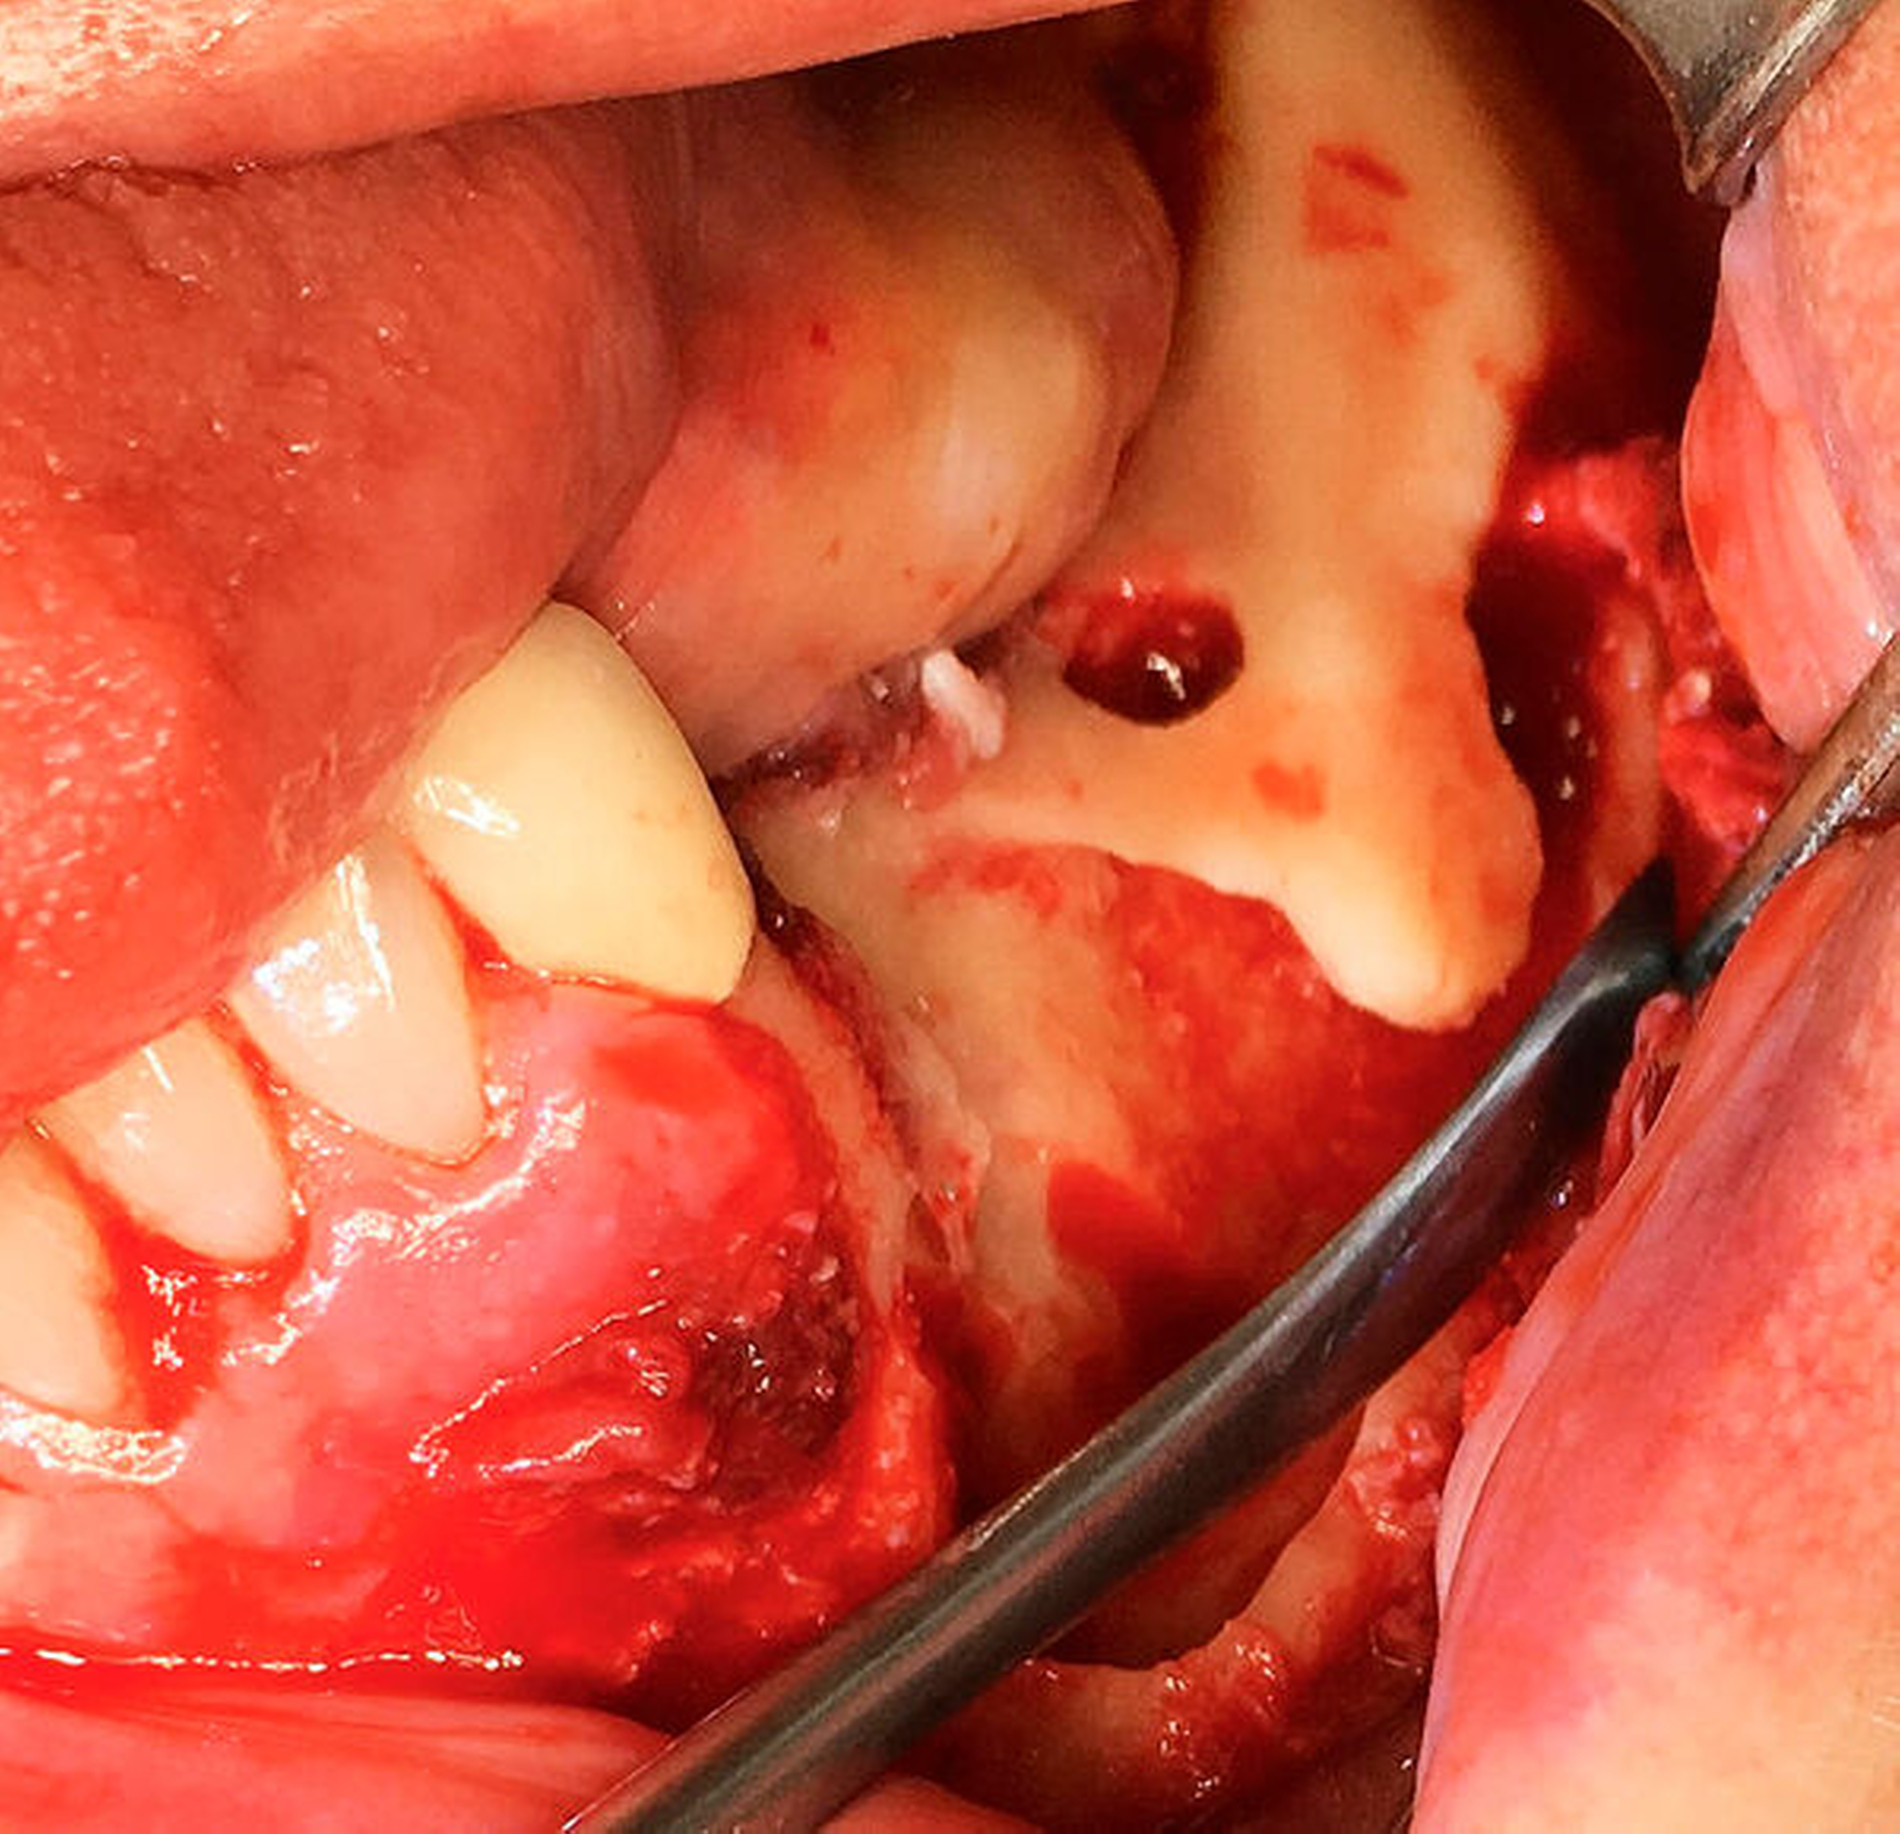

Nach der Entfernung des Wurzelrests 44 wurde der Nervus mentalis am Foramen mentale dargestellt und aus dem umgebenden Weichgewebe frei präpariert (Abbildung 6). Aus der Resektionshöhle und nach Entfernung der vestibulären Knochenlamelle auch aus dem Unterkieferkörper konnte anschließend der Sealer samt der extrem weichen Spongiosa entfernt werden. Die Lage der radiologisch dichten Verschattung im krestalen Bereich regio 36 konnte ebenfalls lokalisiert und problemlos entfernt werden. Bei dem Fremdkörper handelte es sich vermutlich um einen Amalgamrest (Abbildung 7).

Da der Sealer auch entlang des Mandibularkanals nach dorsal überpresst war, wurde zunächst eine Nervlateralisation mittels Piezosurgery durchgeführt. Nach vollständiger Freilegung des Nervs konnte der Sealer nahezu vollständig aus dem Kanal geborgen werden (Abbildung 8).